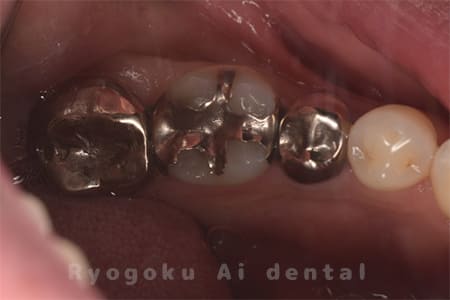

右下の銀歯が外れかかっているとのことでご来院された患者様です。虫歯が大きく、かつ歯が割れており、保存不可能と判断し、親知らずの移植を行いました。